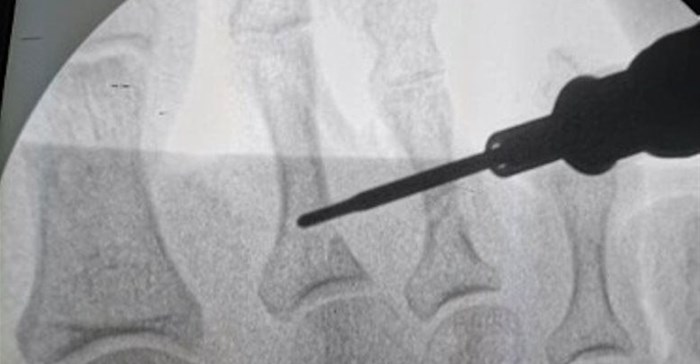

He explains that the development of minimally invasive foot and ankle surgery has been spurred on by the development of two important technologies, namely the burr, which is an instrument used to shape bones, and the endoscope, a tiny camera that enables surgeons to see inside the joints and is used to guide certain minimally invasive procedures.

Mayet has undergone highly specialised, accredited training in Spain and he and his team have already completed a number of minimally invasive surgeries. These have included ligament repairs; correction of foot deformities including bunions; bone fusions, as well as endoscope-assisted surgery to correct various pathologies of the feet and ankles. He says among the most noteworthy of these procedures was the successful correction of bunions and lesser toe deformities.